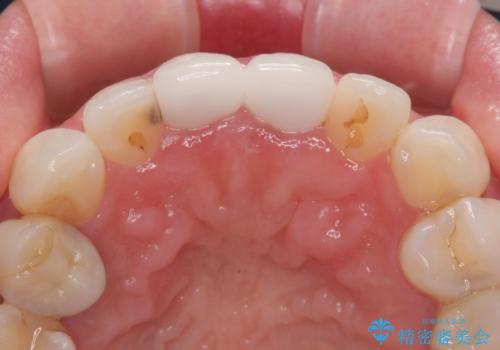

- 前歯の色が黄色くなって気になるとのことで来院された患者様です。

約20年前に前歯の根管治療を行い、保険の被せものを入れたとのことです。

拡大鏡視野下で、被せもの、金属の土台、虫歯を除去し、ファイバーの土台(ファイバーコア)をたてて、オールセラミッククラウンに適した形に整えました。

患者様のご希望で周りの歯も白くしたいとのことでオフィスホワイトニング、ホームホワイトニングで色の調整を行い、色味が落ち着いてから、歯と歯茎の間に圧排糸と呼ばれる糸を入れてシリコーン印象を行いました。